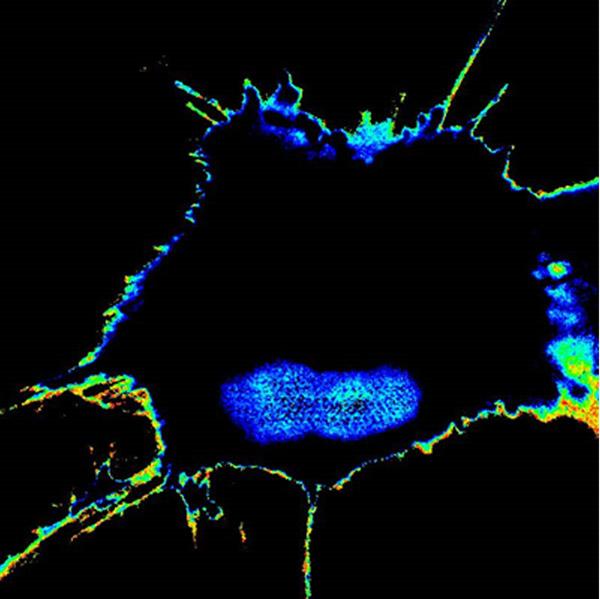

image: A tumor cell that has acquired high metastatic potential during chemotherapy lights up with high FRET biosensor readout, whereas the cells that are sensitive to chemotherapy (and hence, low potential) stays dark.

The team used novel engineered biosensors and sophisticated microscopes to monitor the modification on GIV and found that, indeed, fluorescent signals reflected a tumor cell's metastatic tendency. They were then able to measure the metastatic potential of single cancer cells and account for the unknowns of an evolving tumor biology through this activity. The result was the development of Fluorescence Resonance Energy Transfer (FRET) biosensors.